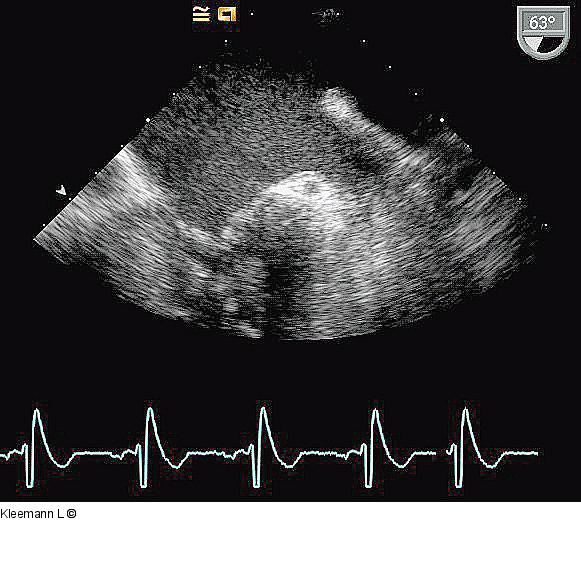

Abbildung 4: Echo TEE 30.07.: unveränderter Befund |